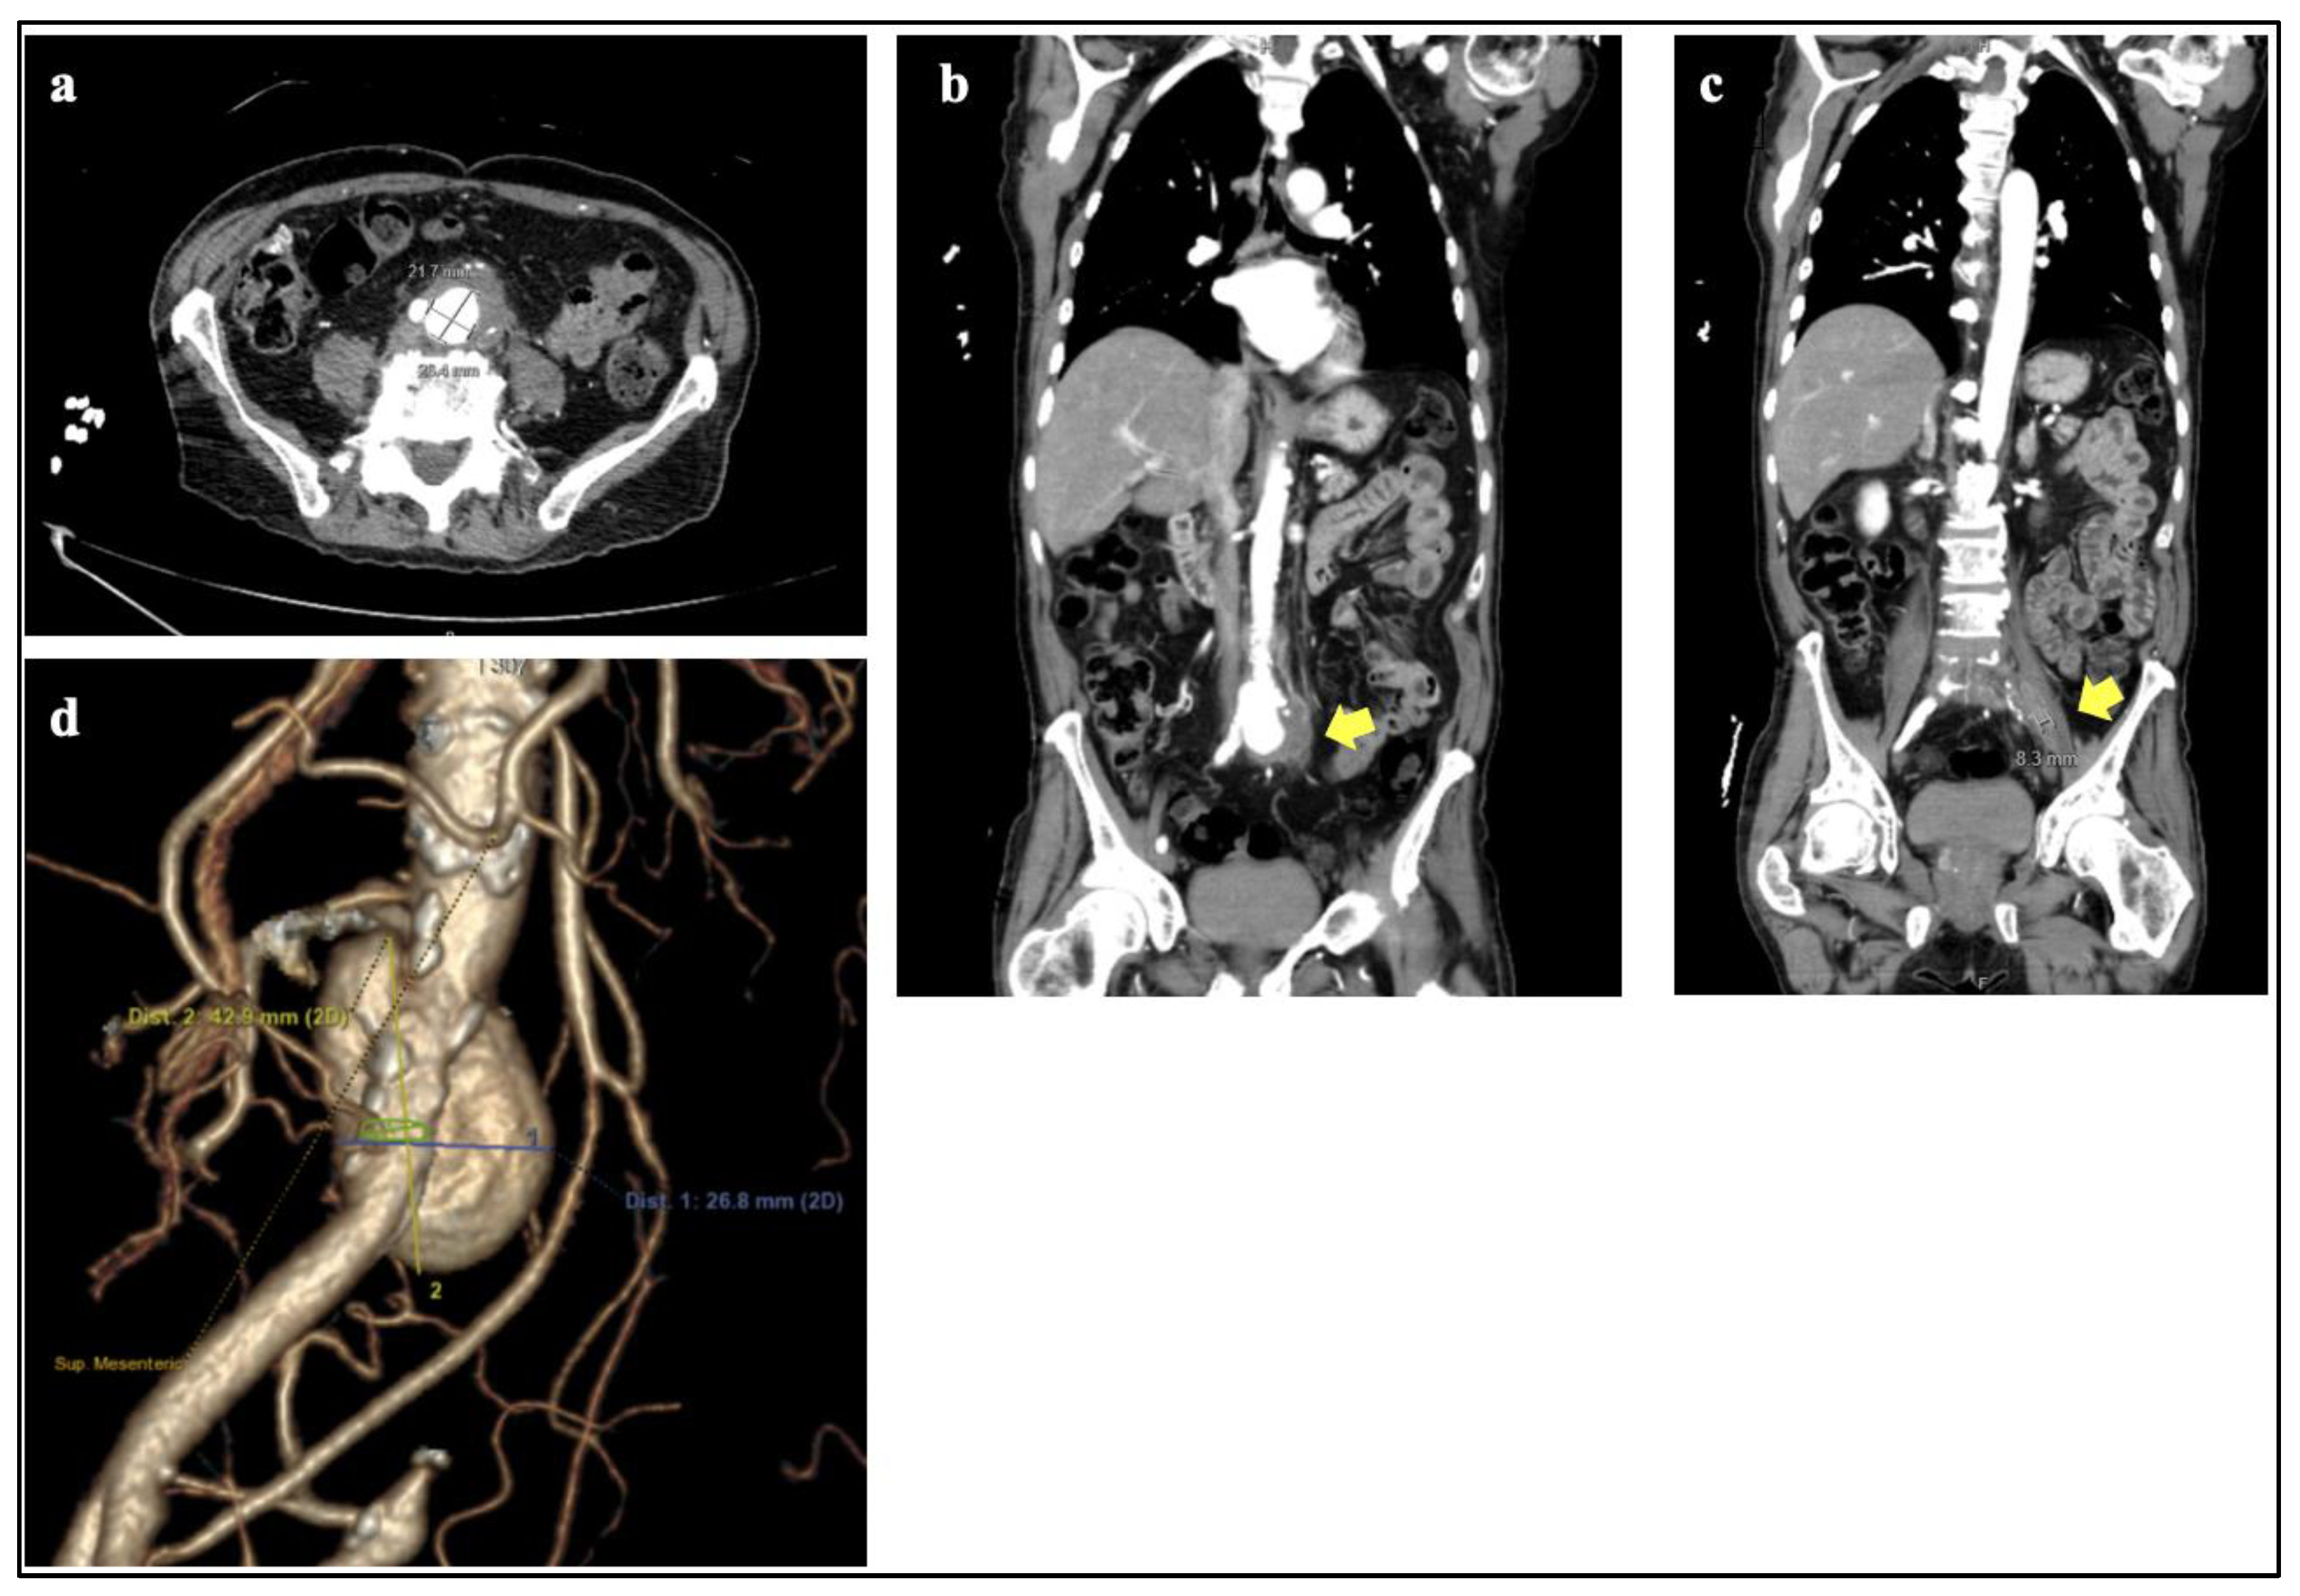

| Our Case | 78M | AAA | L psoas abscess | 30 | 9 | AAA (25 d) | M. tb with pyrazinamide resistance | Open repair with allograft | NA | Cardiac arrest leading to death intraoperatively |